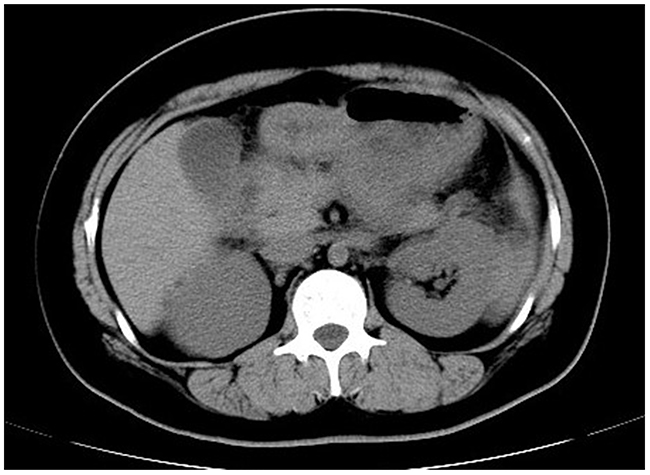

The proband’s niece, MC (II-1), carried more severe hyperlipidemia. She was admitted with symptoms of acute pancreatitis and deleterious lipid profile as evidenced by abnormal plasma concentrations of TG (22.20 mmol/L) and TC (16.34 mmol/L) but low HDL (0.5 mmol/L) and LDL (1.7 mmol/L) (Table 1). The typical computed tomography manifestation further supported the diagnosis of acute pancreatitis (Figure 2). In the context of abdominal pain and hypertriglyceridemia, MC was placed on cessation of oral intake, antacid and alimentary replacement. After the treatment, the plasma triglyceride level decreased to 4.94 mmol/L, but C-reactive protein was still high (26.02 mg/L). She was then prescribed with Chinese herb, Fenofibrate (0.1 g bid), antacid, and a regime of liquid low-fat diet. Her serum triglyceride concentrations still fluctuated, ranging from 6 mmol/L to 8 mmol/L. After amelioration of acute pancreatitis, she was discharged with a prescription of lipid-lowering drugs mentioned previously. However, she still experienced multiple attacks of acute pancreatitis upon digestion of a paucity of red meat, which is a strong indication of genetic deficiency.

Figure 2: Abdominal computed tomography. A typical computed tomography manifestation of enlarged pancreas with blurred outline, disappearance of peripancreatic space and thickened left renal fascia was highly suggestive of acute pancreatitis.